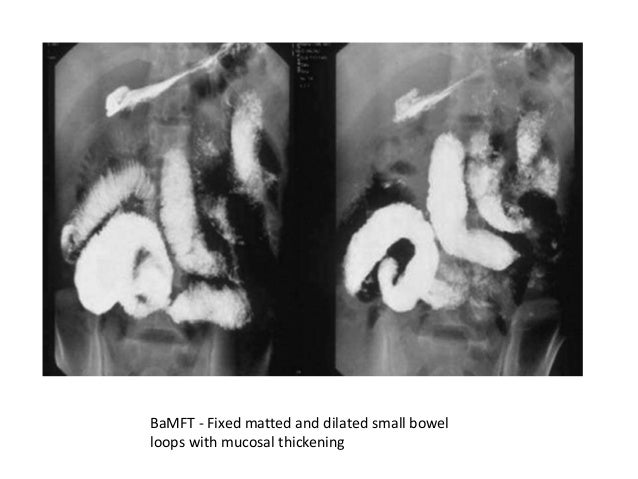

Barium Meal Follow Through Images A A Young Patient Who Was A Known Download Scientific Diagram